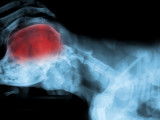

Le cerveau est le principal organe qui constitue le système nerveux du chien. Il fait partie de l'encéphale, qui elle-même appartient au système nerveux central. Il se situe dans la tête, où il est protégé par le crâne (ou boîte crânienne).

Il est considéré comme le chef d'orchestre de l'organisme, dans la mesure où il gère de nombreuses fonctions essentielles : le langage, les mouvements, la conscience, l'intelligence, la mémoire, les perceptions... C'est donc un organe vital.

Il est composé de deux hémisphères : le gauche et le droit, qui gèrent des fonctions différentes. Les hémisphères sont eux-mêmes divisés en 6 lobes : frontal, pariétal, occipital, temporal, limbique et central. Eux aussi se répartissent le travail.

Le cerveau comprend aussi la matière grise, qui contient entre autres les neurones. Elle se subdivise en plusieurs parties : le thalamus, l'hypothalamus, l'épithalamus et le sous-thalamus.